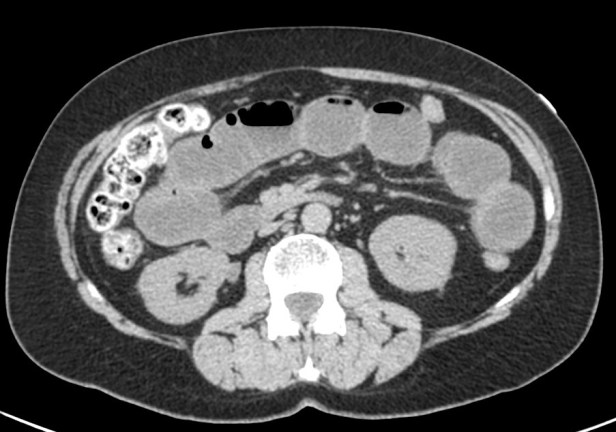

- Dilatación por obstrucción de asas de delgado.

- Aerobilia.

- Litiasis (2 – 3 cm aprox). Hay que tener cuidado ya que muchas litiasis no están calcificadas y su densidad puede ser similar al contenido del intestino. Pueden ser multiples, por tanto hay que poner atención para que no pasen desapercibidas y evitar las recidivas.

Se realiza placa de abdomen y TC en vacío y fase portal.

El cuadro oclusivo está producido por una litiasis biliar que ha pasado de la vesícula al intestino a través de una fístula con el duodeno y que llegó hasta el recto por una insuficiencia de la válvula ileocecal. Así, se produjo una dilatación generalizada de asas, principalmente de las del intestino grueso, que finalmente derivó en isquemia intestinal.